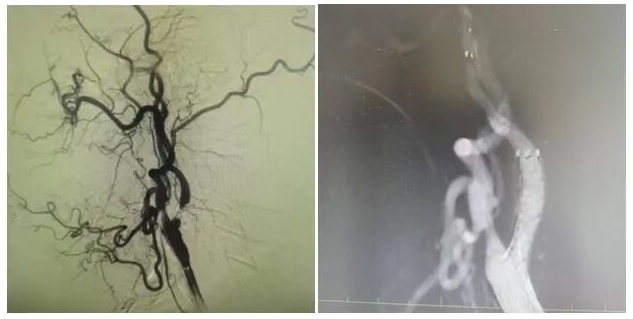

為明確病因,團(tuán)隊為姜大爺安排針對性檢查:頭顱 MRI 彌散成像顯示左側(cè)大腦半球有分水嶺性腦梗死,提示腦組織缺血損傷,頸部 MRA 檢查發(fā)現(xiàn)左側(cè)頸內(nèi)動脈起始處重度狹窄,血流信號減弱。隨后的 DSA(數(shù)字減影血管造影)檢查進(jìn)一步明確,左側(cè)頸內(nèi)動脈起始處狹窄程度超 90%,呈 “閉塞前改變”,血流受阻導(dǎo)致左側(cè)大腦半球供血不足,進(jìn)而引發(fā)腦梗死與抽搐。

手術(shù)當(dāng)天,丁金明主任親自操刀,團(tuán)隊默契配合:在姜大爺右側(cè)腹股溝穿刺股動脈置入動脈鞘,沿鞘送導(dǎo)絲和導(dǎo)管,在 DSA 引導(dǎo)下穿過狹窄部位,用球囊預(yù)擴張后,精準(zhǔn)釋放頸動脈支架。術(shù)后 DSA 顯示左側(cè)頸內(nèi)動脈血流通暢,狹窄解除。手術(shù)歷時 1 小時,姜大爺生命體征平穩(wěn),無并發(fā)癥。